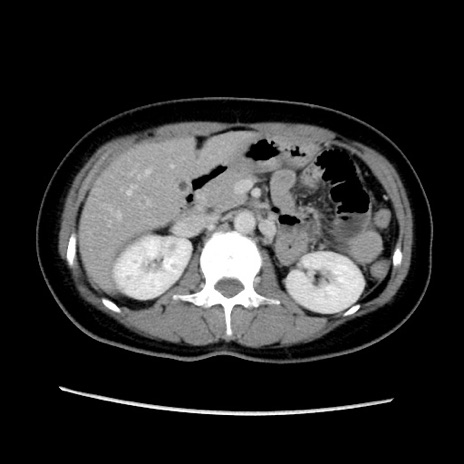

症例39(横断像)

【症例】40歳代女性

【主訴】上下腹部痛

【現病歴】2日目から下腹部痛あり。夜間は痛みで眠れなかった。昨日より上腹部痛と下痢が出現。臥位で痛みは軽快したため、休んでいた。本日になって臥位でも立位でも痛みが強くなってきたため救急要請。

【既往歴】子宮内膜症

【身体所見】部:平坦・軟、左上下腹部に圧痛あり、反跳痛あり。

【データ】WBC 21800、CRP 26.78